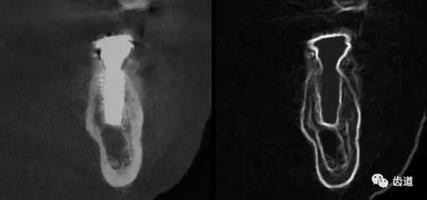

一)牙體牙髓病科

CBCT在牙體牙髓病科治療中,對牙根周圍的解剖關(guān)系、炎癥病變、囊腫等就能夠輕而易舉的進行診斷。甚至與牙齒內(nèi)根管的數(shù)目、走向、分支等都能夠通過牙科CT進行展示,使臨床醫(yī)生的根管治療不再是完全憑手感的“經(jīng)驗科學(xué)”。通過CBCT,還可以對一些“久治不愈“的疑難病例進行檢查和診斷,例如根縱列的診斷、根管內(nèi)異物的定位等,找準(zhǔn)了原因,結(jié)合先進的治療技術(shù)因病施治,使疑難病例的治療變的輕松起來。

1、牙髓根管治療

1)根管治療中牙膠尖充填在CBCT中的影像

2)根管測量